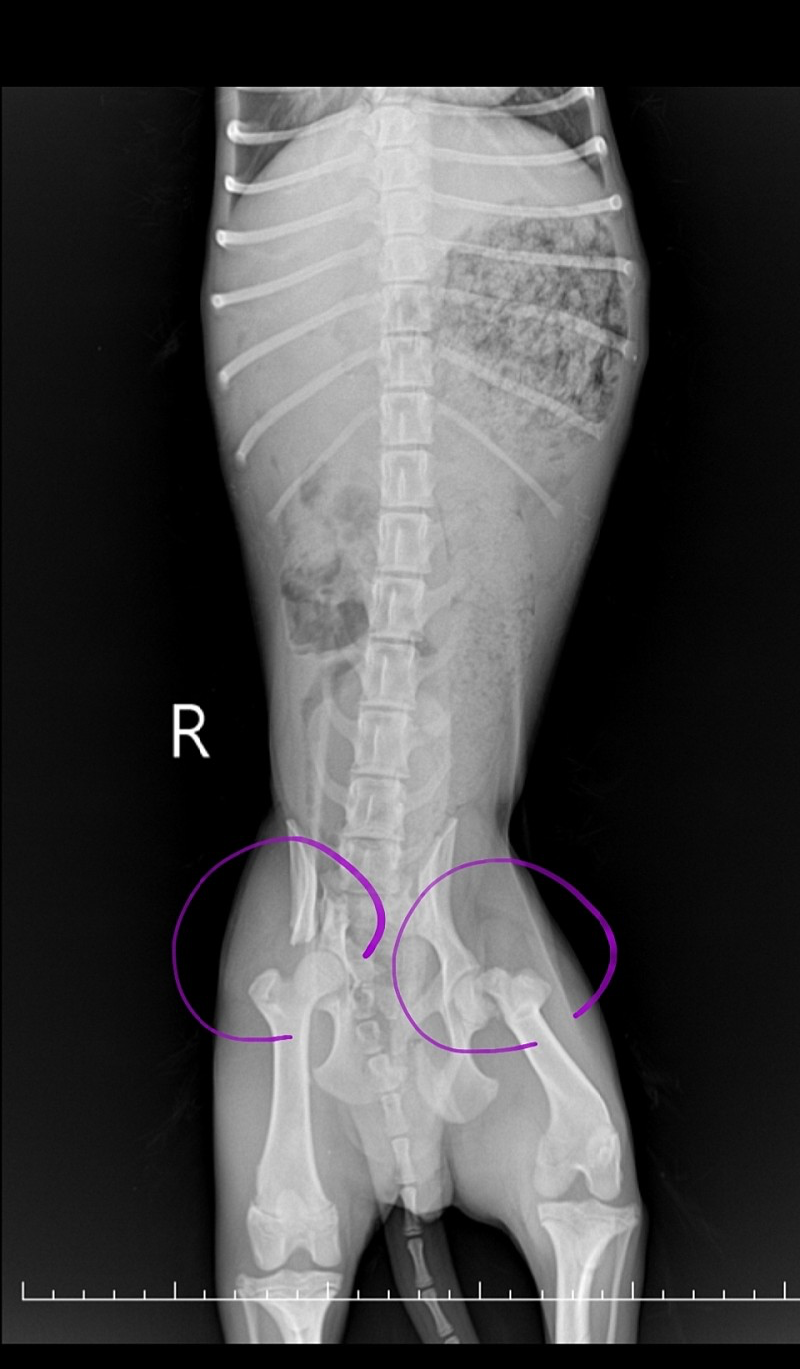

이곳에 오기까지 아이의 생활은 상상도 못 할 지경이었다. 하지만 내가 모든 강아지를 책임질 것도 아니면서 어설픈 동정심으로 섣불리 나설 수도 없었다. 공고번호 2020-00416 이 아이는 어쩐 일인지 걷지 못했다. 아이는 다리가 부러져 있었다. 도대체 너의 세상은 무엇이었을까.

커뮤니티에서 모금을 시작했고, 아이는 수술을 받을 수 있었다.